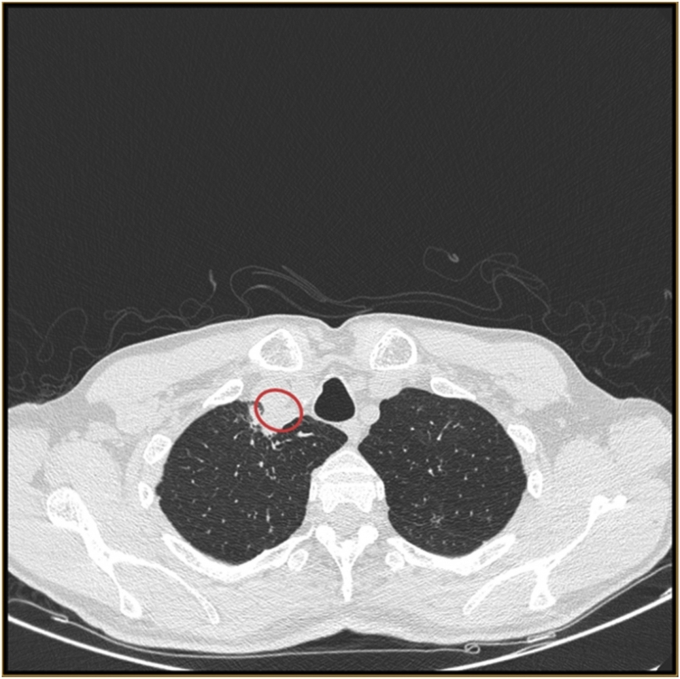

이 남성은 석달간 쉰 목소리, 기침, 피로, 목넘김 어려움 등의 증상으로 고통을 호소하다 병원을 찾았다. 병원에서 CT촬영결과, 이 남성의 목에서 기관지성 낭종이 발견됐다. 원인을 쉽사리 특정할 수 없었던 담당 의사는 낭종에서 짜낸 고름 샘플을 세계보건기구(WHO) 협력센터에 보내 검진을 의뢰했다.